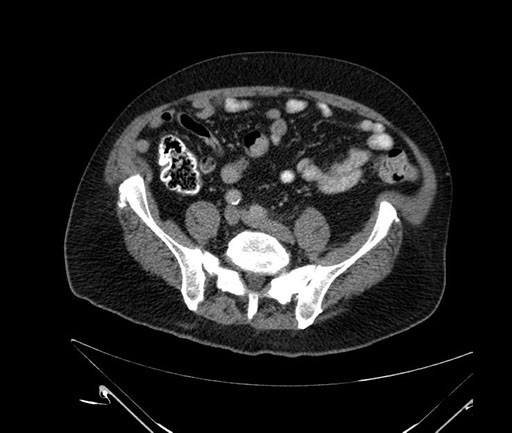

Whipple (pancreaticoduodenectomy) [case 7]

Axial - stented